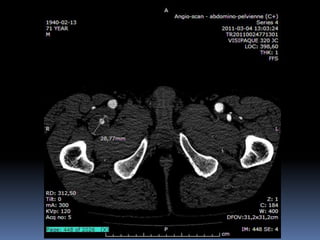

Cas # 1 ♂ 71 ans entrepreneur…  ATCD  PABI ’99  Investigation ‘2011  FCD 35 mm  FPD 30 mm  Popl D 35 mm  Popl G 23 mm  FCG 18 mm

72 59 ATCD: PABI’99 re: AIliaquebil ATCD: Db , ROH Korsakoff, MCASPAC, fempop bilat Anévr popl. Suivi Anévr fém et popl RC: référé rupture…en fait «non» mais symptomatique Quest: … Quest.:C.I. non limitante E.P.: masse puls. > 5cm ing. D non doul et autres… E.P.: masse pulsatile >5 cm ing G doul palpation, nécrose sèche extr dist un orteil non doul Pls périph N Doppler Angioscan: dimensions anévr. ? Angioscan: dimensions Anévr ?

Cas #1 72ans Cas #2 59 ans  Suivi  ATCD  PABI  Particularités  Anévrysme Fémorale profonde  Cutler-Darling type 1  Symptomatique  ATCD  Fem-pop. Bilatéraux…  Particularités  Korsakoff  Cutler-Darling type 2 thrombosés